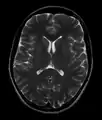

- T2-weighted (T2W) images: CSF is light, but fat (and thus white matter) is darker than with T1. T2-weighted images are useful for visualizing pathology.[26]

- Normal axial T2-weighted MR image of the brain